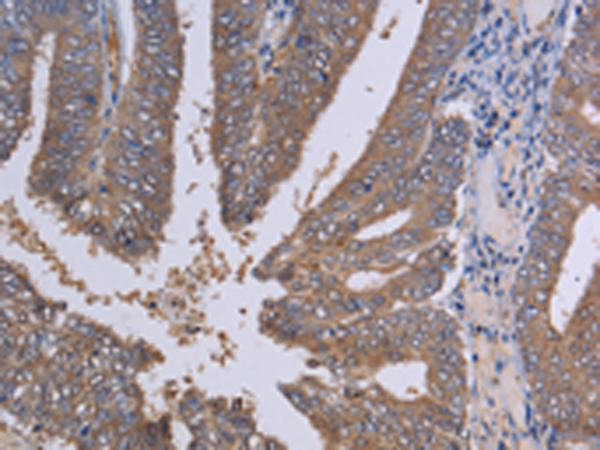

分类: 科研抗体货号: P08481别名:应用: IHC反应种属: Human, Mouse